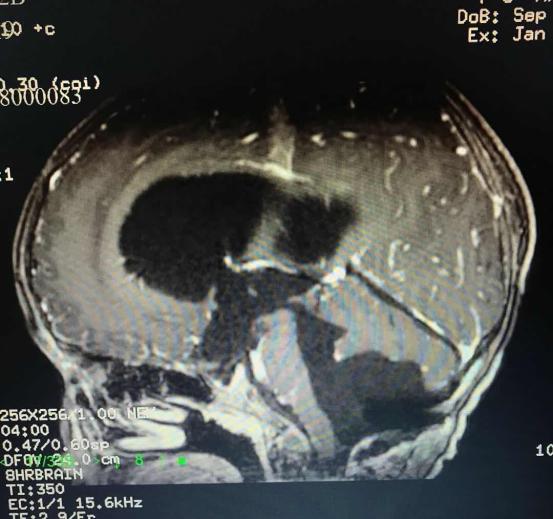

*术后CT影像资料*

术后小乐预后良好,术前症状消除。